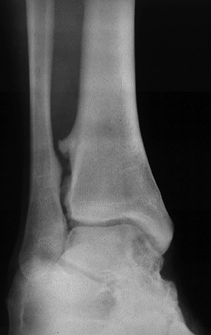

tenderness is present, include the entire tibia and fibula to avoid

missing an extensive syndesmosis rupture with associated proximal

fibula fracture. On the AP view, the fibula should overlap the tibia by

42% of the width of the fibula, and on the mortise view the separation

of the tibia and fibula should not exceed 5 mm (30). A comparison view is helpful (Fig. 95.9).

Radiographic evidence of lateral talar shift in the absence of a fibula

fracture confirms combined rupture of the deltoid ligament and

syndesmosis (Fig. 95.10). If latent diastasis is suspected, obtain a stress AP or mortise view by applying external rotation to the foot and ankle.

| Figure 95.9. Syndesmosis disruption (A) compared to normal mortise (B). |

| Figure 95.10. Lateral talar shift confirming deltoid ligament tear associated with syndesmosis rupture. |